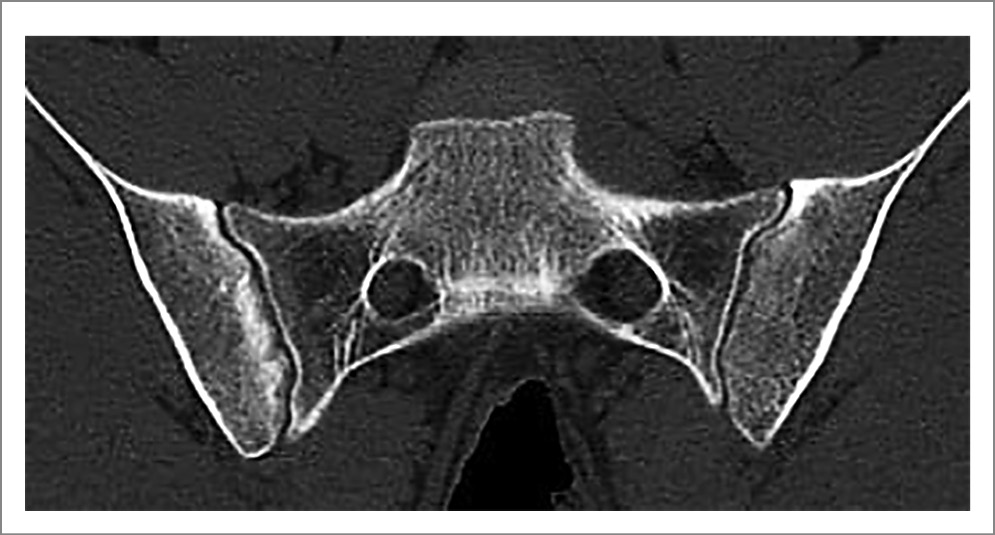

Иллюстрации типичного сакроилиита у пациентов с АС приведены на рис. 3 и 4.

Рис. 3. Пациентка Б. 22 лет, диагноз АС, длительность болезни 36 мес. КТ крестцово-подвздошных сочленений (коронарная проекция): широкий субхондральный склероз в подвздошных костях, справа мелкие эрозии в верхней части и участки расширения щели в нижней части сустава, слева множественные эрозии и участки расширения щели (двусторонний определенный сакроилиит).